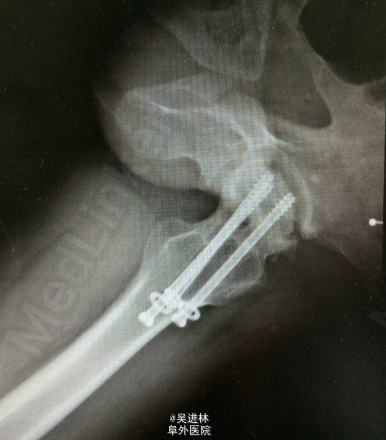

最近新收入院数例患者,都非常年轻,因为车祸后股骨颈骨折行钢钉固定,固定术一年后无明显诱因出现髋部疼痛,活动度受限,X线提示股骨头坏死。现在面临的唯一选择就是全髋关节置换术。据国外学者统计,股骨颈骨折术后股骨头坏死的发生率可以高达30%。所以,对于garden分型三四期的病人,最好选择全髋置换术,一次性解决问题。